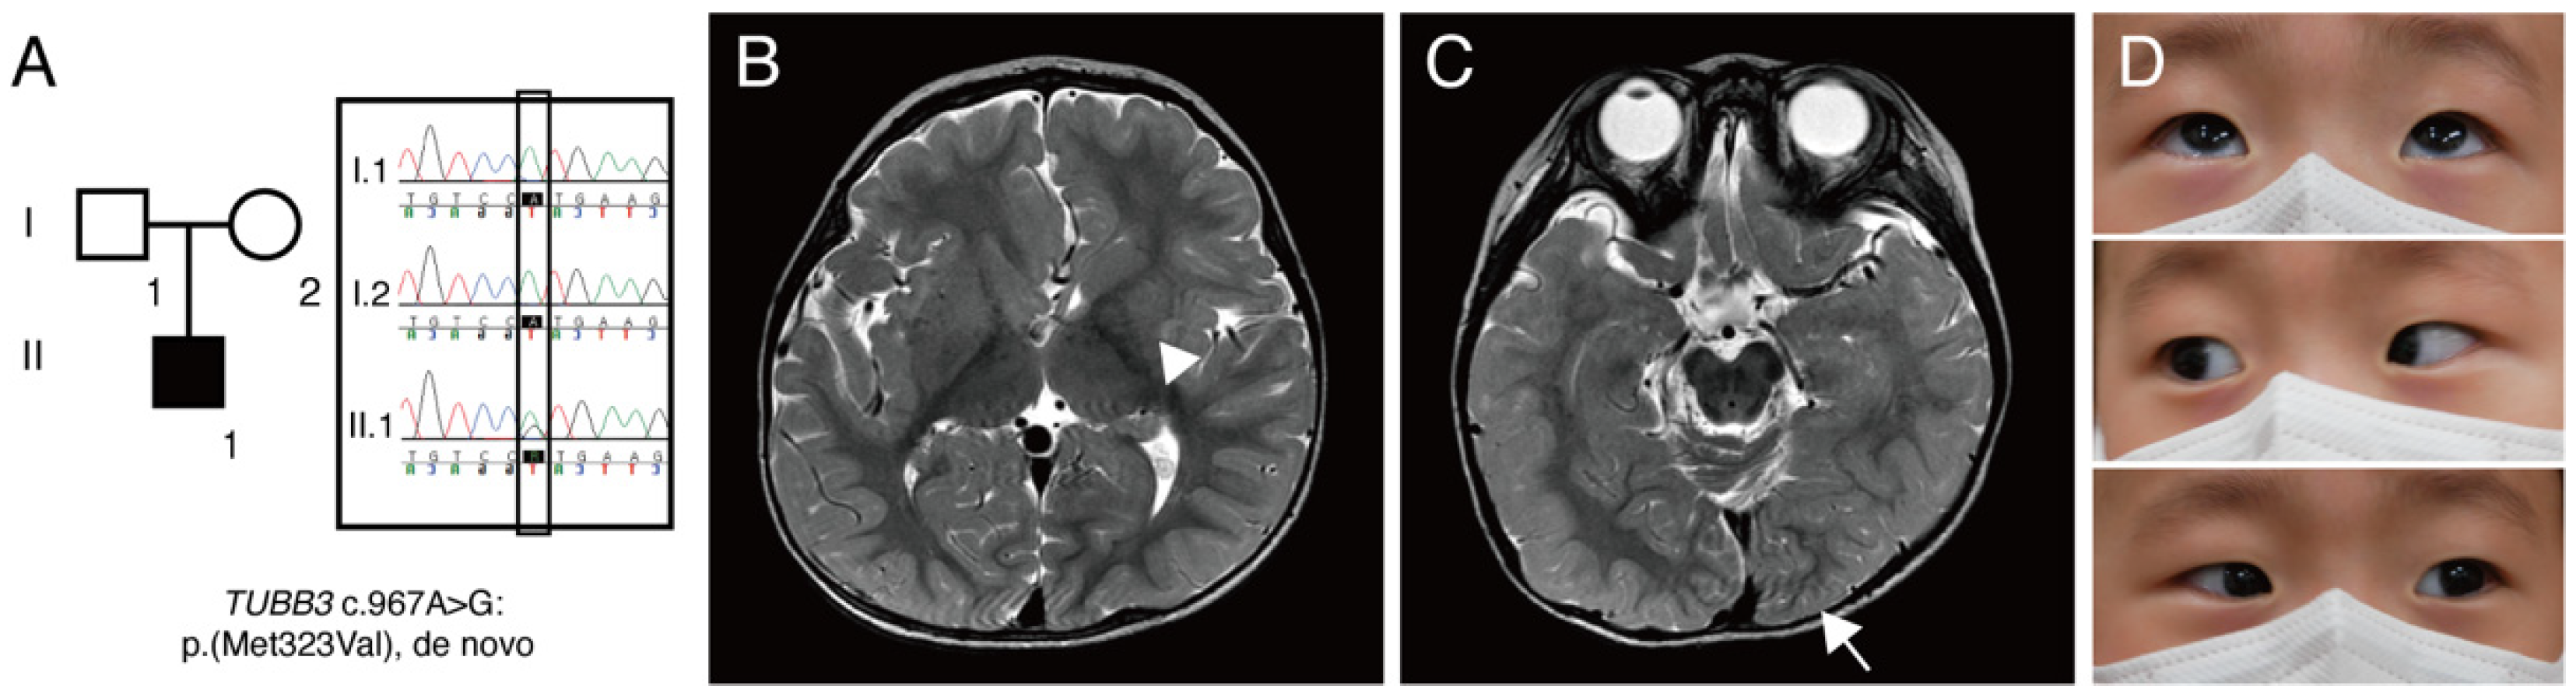

On initial examination, he could not fix his eyes on an object and follow, and 1–2-Hz pendular nystagmus was noted. Cycloplegic refraction showed +sph1.50 in the right eye and +sph2.00 in the left eye. He had neither eye-poking signs nor photoaversion. Dilated fundus examination showed normal foveal reflex and normal optic disc at the posterior pole. An extraocular motility test showed a full range of motion. The neurological examination was also unremarkable. Targeted NGS revealed a heterozygous missense c.967A>G:p.(M323V) variant [Chr16(GRCh37):g.90001826A>G] in the TUBB3 gene (NM_006086.4). This variant is absent in the population databases, such as the Genome Aggregation Database (gnomAD), the 1000 Genomes Project, and the Korean Reference Genome Database. This genomic position is highly conserved (phastCons: 1.00 and phyloP: 4.64). The M323 residue is located in exon 4 and conserved across β-tubulin isotypes from chicken to humans. Multiple lines of computational evidence support a deleterious effect of this variant (CADD: 25.0, FATHMM: 0.992). It was previously reported as pathogenic in ClinVar (RCV000023202.4). A de novo mutation was confirmed through segregation analysis (Figure 1A). This variant was classified as pathogenic (PS2, PM1, PM2, PP3, and PP5) according to the guideline of the American College of Medical Genetics [23].

(A) A pedigree of patient reported in this study. Square, male; round, female; black coloring, affected individual. Targeted next-generation sequencing showed TUBB3 c.967A>G:p.(M323V) variant. Sanger sequencing confirmed that this variant is a de novo mutation. (B) Brain magnetic resonance imaging showing cortical dysplasia. T2-weighted images without contrast revealed an asymmetric caudate nucleus (arrowhead) and globular shape of both basal ganglia and thalamus. (C) Axial T2-weighted image showing an asymmetric configuration of an occipital lobe (arrow) and abnormal cerebellar vermian foldings. (D) Pictures of an extraocular motility examination showing a full range of motion.

Subsequently, brain magnetic resonance imaging (MRI) was performed, and it revealed an asymmetric configuration and size of caudate nuclei and asymmetric configurations of lateral ventricles, occipital lobes, and corpus callosum, which are consistent with cortical dysplasia (Figure 1B,C). Repeated examination of extraocular motility had shown full duction and version until the age of 23 months (Figure 1D), and 2-Hz left-beating jerk nystagmus and intermittent head nodding were observed. A non-sedated hand-held ERG test (RETeval, LKC Technologies, Gaithersburg, MD, USA) using skin electrodes was performed for the diagnosis of retinal dysfunctions associated with nystagmus. The scotopic response was normal, but the result was inconclusive due to poor patient cooperation (Figure 2). Neurological examinations showed no gross or fine motor delays. He could sit, walk, and even run without support, but mild intellectual disability and mild language delay were noted.